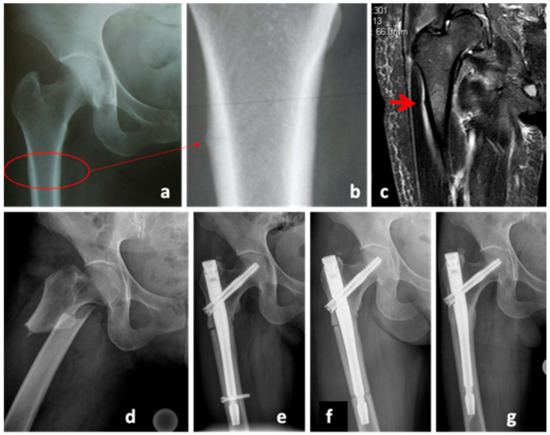

A 50-year-old female Caucasian patient (body mass 66 kg; height: 165 cm; BMI: 24.2 kg/m2) presented with a multifragmentary fracture of the left clavicle (AO 15.2C, non-dominant arm) after a bicycle accident (Figure 2a). Due to fracture comminution and shortening of the clavicle of more than 2 cm, an operative treatment was indicated. The patient was treated with an open reduction and internal fixation (ORIF) and plate osteosynthesis (LCP Reconstruction Plate 3.5, DePuy Synthes, USA) (Figure 2b). Serial X-rays during the first 6 months showed no radiological signs of union and the patient was diagnosed with an atrophic delayed union. She was referred for osteological treatment (Figure 2c). Due to inadequate Vitamin D levels and low calcium intake, both were supplemented. There were no further predisposing factors for nonunion. The radiological analysis showed a lack of contact between the bony fragments (Figure 2c. However, the patient was pain-free and, therefore, the decision against further surgery was made. A treatment with teriparatide was initiated. Subsequent biomarker analyses revealed a 61% increase in P1NP and a 208% increase in Beta CT-x after 3 months of treatment. However, there were no radiological signs of union. A single-photon emission computed tomography (SPECT-CT) after 11 months of teriparatide treatment showed no biological activity at the fracture zone (Figure 2d). Consequently, the patient was informed about the high risk of implant failure and low chance of fracture healing. Due to the fact that she was still pain-free and showed no signs of relevant impairment in the activities of daily living, she decided against an operation. As expected, the patient presented with plate failure 18 months after the initial surgery (Figure 2e). The plate was removed, and an ORIF with autologous tricortical iliac bone graft (LCP 3.5 mm Plate, DePuy Synthes, USA) was conducted (Figure 2f). The teriparatide treatment was continued. The further course was uneventful and clinical and radiological bone union was achieved 6 months postoperatively (Figure 2g).

Figure 1. Case 1, X-Rays and MRI of the femur on the day of initial presentation (ac) and one day later (d), showing the diagnosis of an atypical femoral fracture (AFF) under bisphosphonate therapy. X-ray of the hip, 7 months after trauma in the presence of a delayed union (e), after nail dynamization (f), and at the end of the teriparatide therapy (g), 31 months after trauma.

Figure 3. Case 3, x-ray showing the initial periprosthetic humeral fracture (UCS I.1B1) (a,b), the initial postoperative radiograph (c), delayed union 6 months after trauma (d) and bone union at the end of the teriparatide treatment, 12 months after trauma (e).